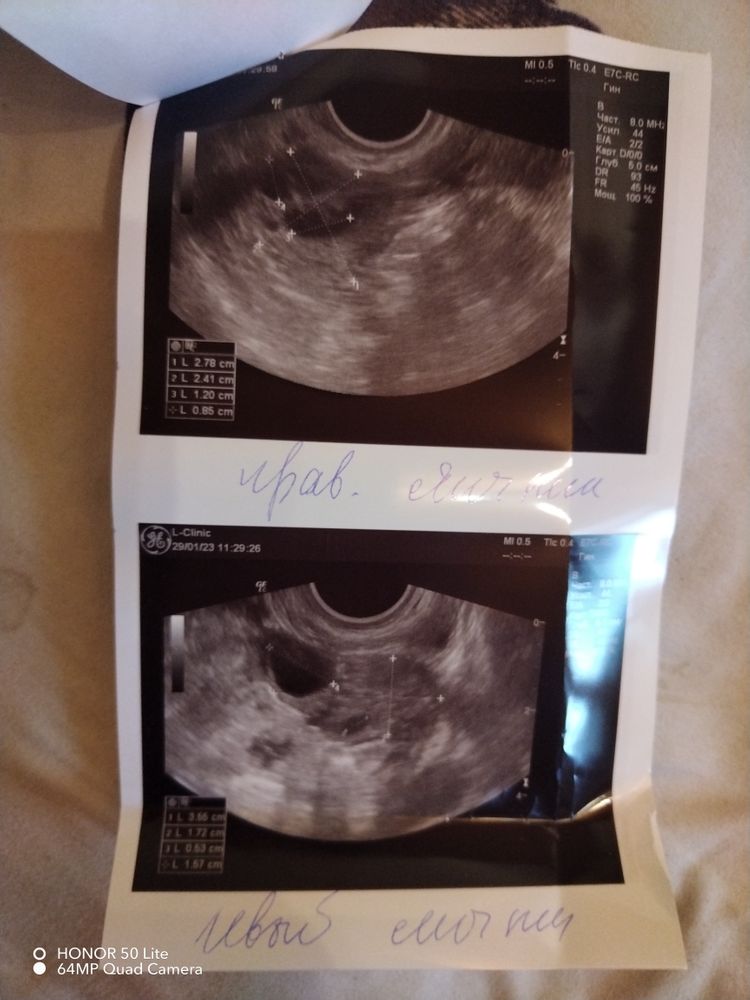

26дц, фолликулометрия 😊

У вас уже овуляция была)) в левом яичнике лопнул 😊

Шохида , это-то я поняла) а жидкостные включения и размеры-это кисты с такими размерами?

Ирис_Ка, У вас нет кисты )) с размерами все хорошо 🙈 откуда взяли что у вас кисты

Шохида , а жидкостные образования и включения с размерами-это что?) в инете прочла, что кисты🙈

Ирис_Ка, У вас же с левой стороны овуляция была поэтому там и есть жидкость 😊 если вам узистка ничего не сказала то все хорошо 😉

Шохида , жидкости нет😐есть именно жидкостные включения и образования с размерами от 6-7 мм до 12-16мм🤷‍♀️